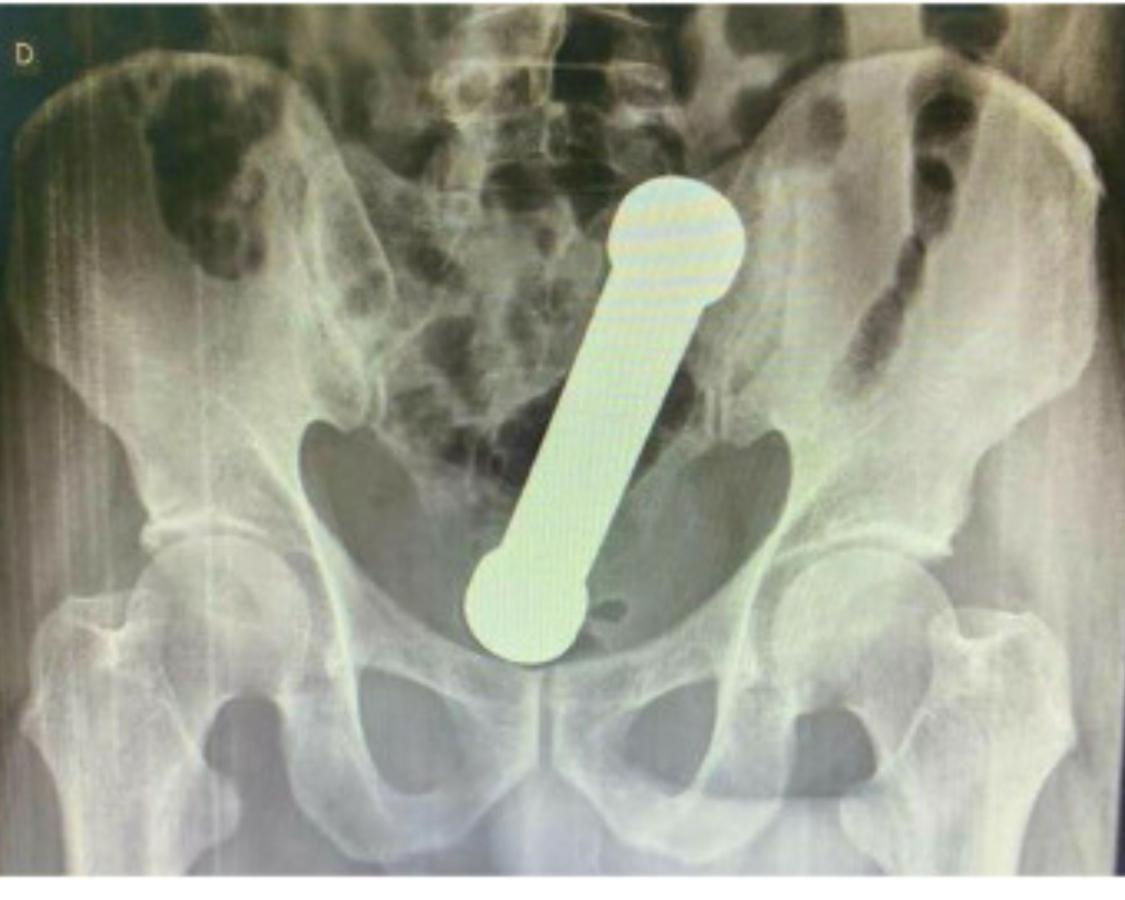

Las radiografías abdominales revelaron que el hombre tenía una mancuerna de 20 centímetros atorada a la altura del lugar en que el colon se conecta con el recto.

Luego de que salieran a la luz los resultados de los exámenes, el hombre confesó que dos días atrás se había introducido la pesa metálica de dos kilos por motivos sexuales. Lamentablemente, después no pudo extraer el objeto de su interior.